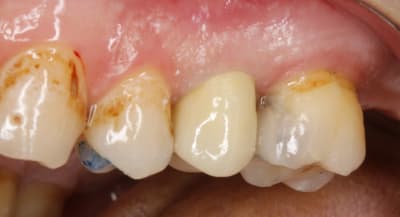

et là ç est le 1 er jour , le jour de l endo .

le but est de pretailler la dent en restant juxta .

en aucun cas ,il faut toucher la gencive le 1 ere séance . ( sauf s'il y a carie bien sur , mais ç est tres ponctuel ).

la seance d apres , alors que l on a pas touché la gencive , hein , et bien elle va se rétracter , pcq elle sera stimulée mecaniquement .

voilà , ce matin on est donc à 1 semaine .

on voit que la gencive ç est tassée .

je dis tasseé pcq on ne peut pas dire cicatrisée puisqu on ne l avait pas touché la semaine passée .

on peut mettre 1 fil , et meme se servir du chausse pied , ça ne saignera pas , ç est du beurre .

et on reprecise les limites à la grain fin .